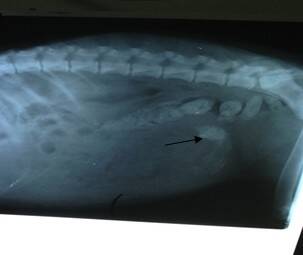

X光检查:除明显直肠粪便外,肠管内异物(箭头所指处)

肠管内异物